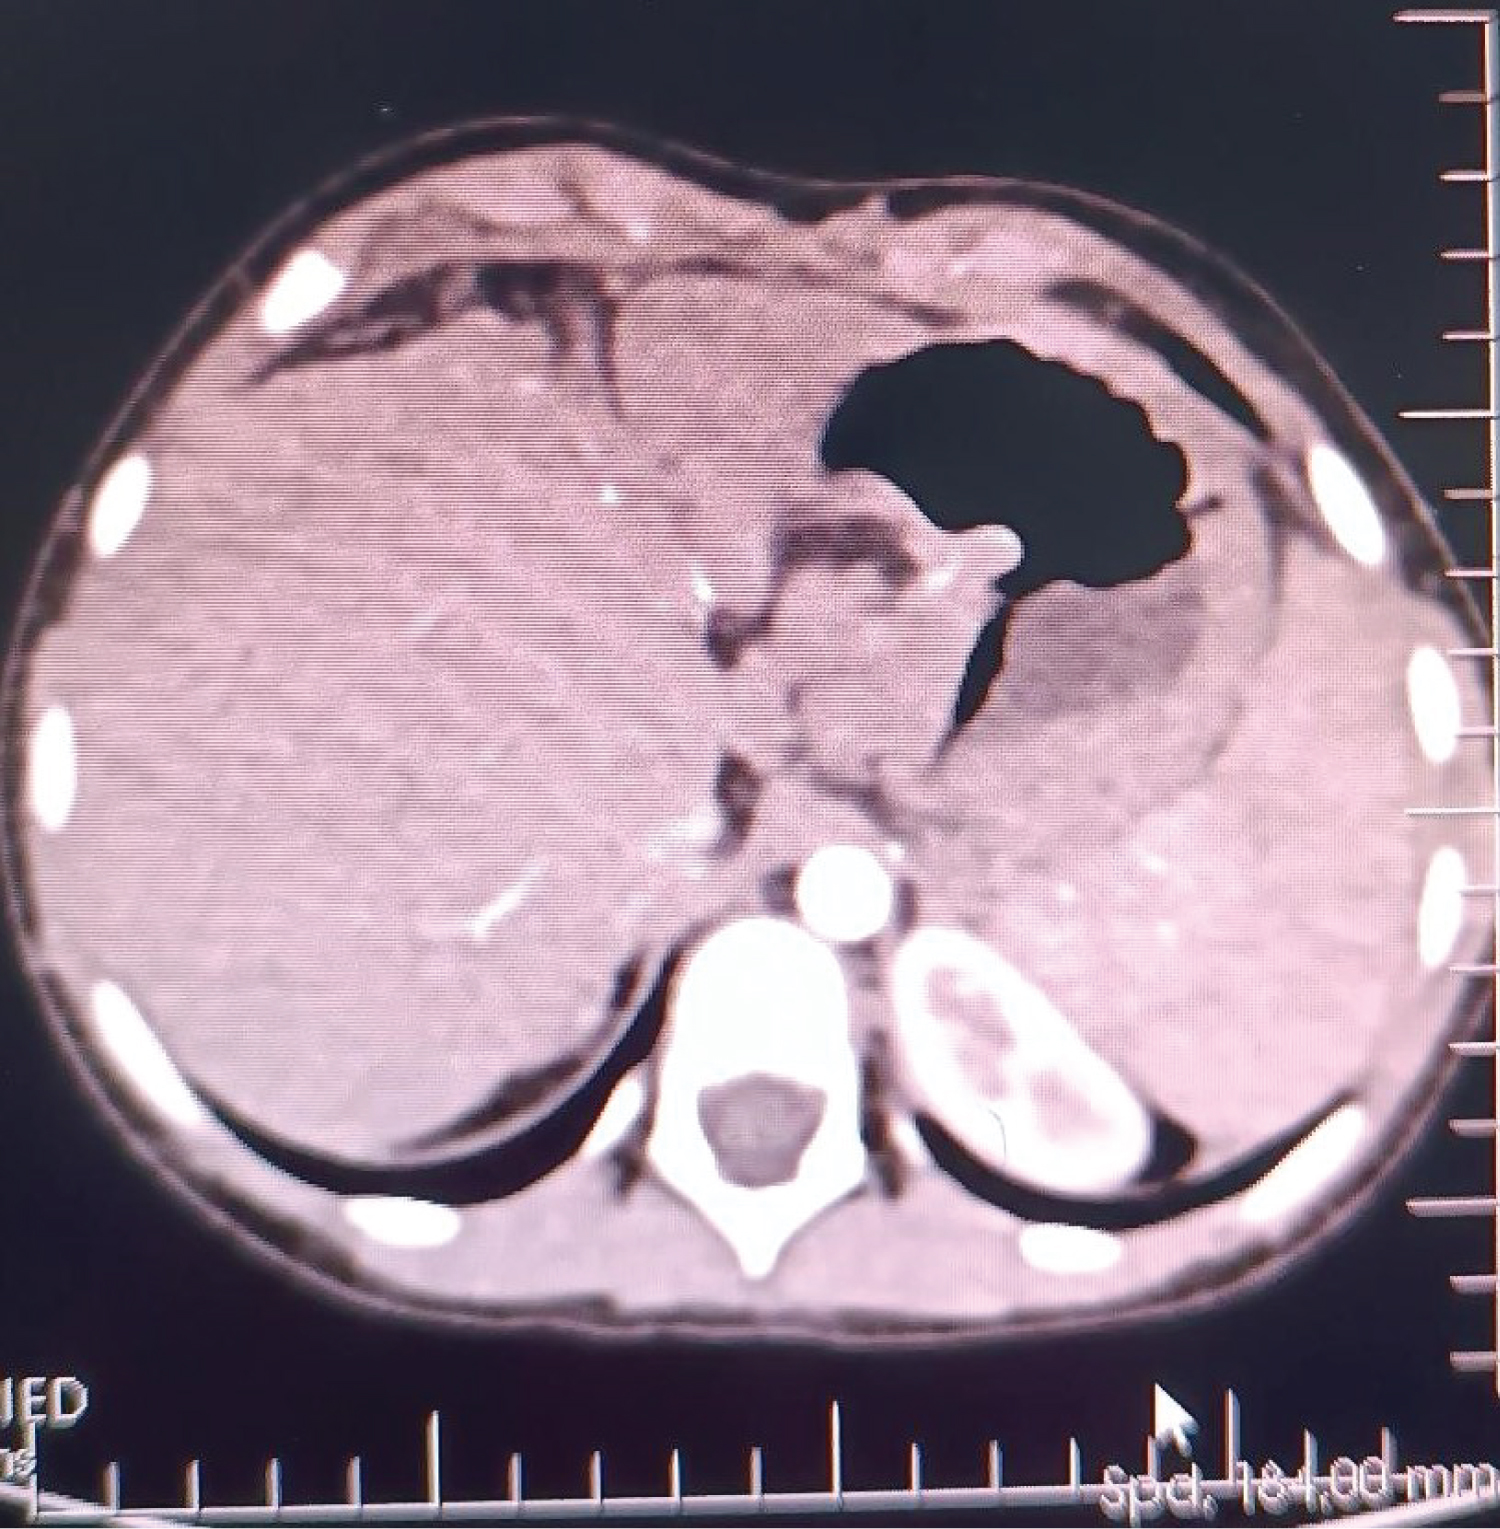

We aimed for mean arterial pressure (MAP) > 60 mmHg throughout the operation. 560g of liver tissue was removed from the patient (Figure 2). After the anastomoses of the great vessels were completed in the anhepatic phase of approximately 45 minutes, the clamp on the portal vein was removed, and reperfusion was achieved. The patient's blood pressure fell to 66/34 mmHg 2 minutes after reperfusion. The norepinephrine infusion dose was increased until his hemodynamics stabilized, and 5 mg of ephedrine and 100 mg of calcium chloride were given twice. In the intraoperative period, transesophageal echocardiography (TEE) provides invaluable information for closely monitoring pulmonary vascular resistance (PVR) and right ventricular functions in these patients. Since our patient had esophageal varices, we did not perform direct TEE, but when an extraordinary event occurred, we kept her at the patient's bedside to do it quickly. Our patient did not have pulmonary hypertension in the preoperative examination, and we tried to minimize the triggering factors that would increase PVR throughout the operation. We did not detect any increase in PVR in the measurement we made with PiCCO during the neo-hepatic phase. In the neo-hepatic phase, the dose of norepinephrine was reduced as the patient's hemodynamics returned to normal. Fluid therapy was performed considering the PiCCO parameters. The estimated blood loss during surgery was less than 250 mL. During the surgery, the patient was given a total of 1300 mL crystalloid, 1300 mL 5% albumin-containing colloid and 200 mL cell-caver, and 450 mL urine output was achieved. The inserted liver weighed 285g (Figure 3), and the operation continued for 7 hours. After the operation, she was taken to the intubated ICU and connected to a mechanical ventilator. While the patient was being followed on the ventilator, her SaO 2 was between 0.46 and 86-92%. On the 2 nd postoperative day, SaO 2 remained at 90-95%, hypoxemia resolved, weaning was applied, and the patient was weaned from the ventilator. After 2 days of oxygen support with a 2 L/min mask, she breathed in normal room air. After extubation, the patient's general condition and neurological examination were normal. Blood gas values, lactate level and hepatic transaminases returned to normal within days. Immunosuppressive drugs, steroids and nutritional support were administered to the patient. The patient was transferred to the service on the 4 th day after her follow-up in the ICU, and her follow-up continued. The patient was discharged 15 days after the operation without complications in the postoperative period.

Figure 2: 560g of liver tissue was removed from the patient.

Figure 3: The inserted liver weighed 285g.